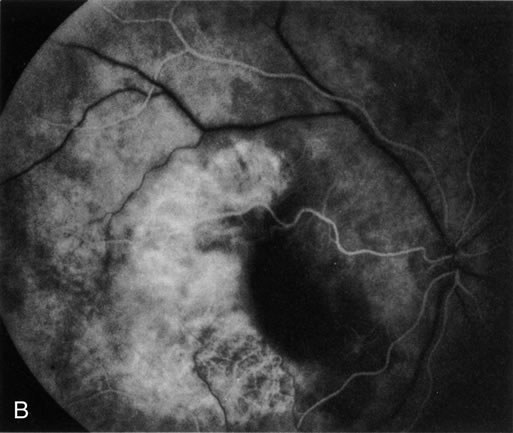

Age-related macular degeneration (AMD) may be divided into two types. Nonexudative (“dry”) AMD has several morphologic forms, including “hard” discrete drusen, shallow retinal pigment epithelial detachments associated with thickened Bruch's membrane (“soft” drusen), and geographic atrophy (GA) of the retinal pigment epithelium (RPE).3 On FA the area of GA appears hyperfluorescent for window defect from the early frames of the angiogram, with late staining of the underlying sclera (Fig. 1). However, these pathologic changes can usually be assessed by clinical examination, and FA is generally not necessary to diagnose nonexudative AMD. An exception is cuticular drusen, which may appear clinically as a subtle disturbance of the RPE; FA reveals multitudes of small, discrete drusen described as “stars in the sky” (Fig. 2). The second type of AMD, which is associated with soft drusen, is known as exudative (“wet”) AMD. It is due to a choroidal neovascular membrane that has incompetent vessels resulting in detachments of the RPE and the neurosensory retina. Consequently, in patients with a large RPE and/or serous neurosensory detachment, FA is often necessary to rule out a choroidal neovascularization (CNV). In general, a small pigment epithelium detachment (PED) and a larger neurosensory detachment overlie CNV, while the opposite is generally the case in a nonexudative PED. Additionally, CNV often presents as a “notched” PED (Fig. 3).4 The presence of subretinal blood or pigment at the border of a PED strongly indicates that the detachment is exudative in origin (Fig. 4). Similarly, a rip in the RPE generally reflects subretinal fibrosis from a CNV (Fig. 5 and 6). The diagnosis is more difficult in patients who have a chronic, organized PED. Such a lesion may be due to either nonexudative AMD or to an organized, fibrotic CNV. Clinically and angiographically, it may be impossible to distinguish between these two conditions. In most cases, however, FA does assist in making the diagnosis.

Fig. 5. A. Clinical photograph of a large, crescent-shaped rip of the retinal pigment epithelium (RPE) in the temporal macula. B. Early-phase fluorescein angiography study demonstrates the presence of a window defect corresponding to the RPE rip, which exposes the choroidal vasculature. Where the RPE is redundant in the central macula there is blockage of the normal choriocapillaris fluorescence. C. Late-phase angiogram reveals intense hyperfluorescence seen through the RPE defect.